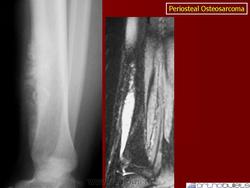

Рентгенологически обнаруживается преимущественно диафизарная локализация; прилежащий к опухоли кортикальный слой утолщен; костномозговой канала не вовлечён эндостальная поверхность кортикальной кости не изменена. Края минерализованной порции опухоли нерегулярной формы и иногда формируют радиально расположенные по отношению к оси кости, спикулы.

Остеосаркома периостальная

Рентгенологическая картина выявляет очаг поражения на поверхности кости. Очаговые фокусы кальциноза, формирование спикул, нечеткая граница опухолевого узла, мягкотканный компонент, отсутствие поражения медуллярного отдела кости, все названные рентгенологические признаки характерны для периостальной остеосаркомы. Для выявления характера поражения костномозгового канала проводится дополнительное исследование с применением КТ и МТР.